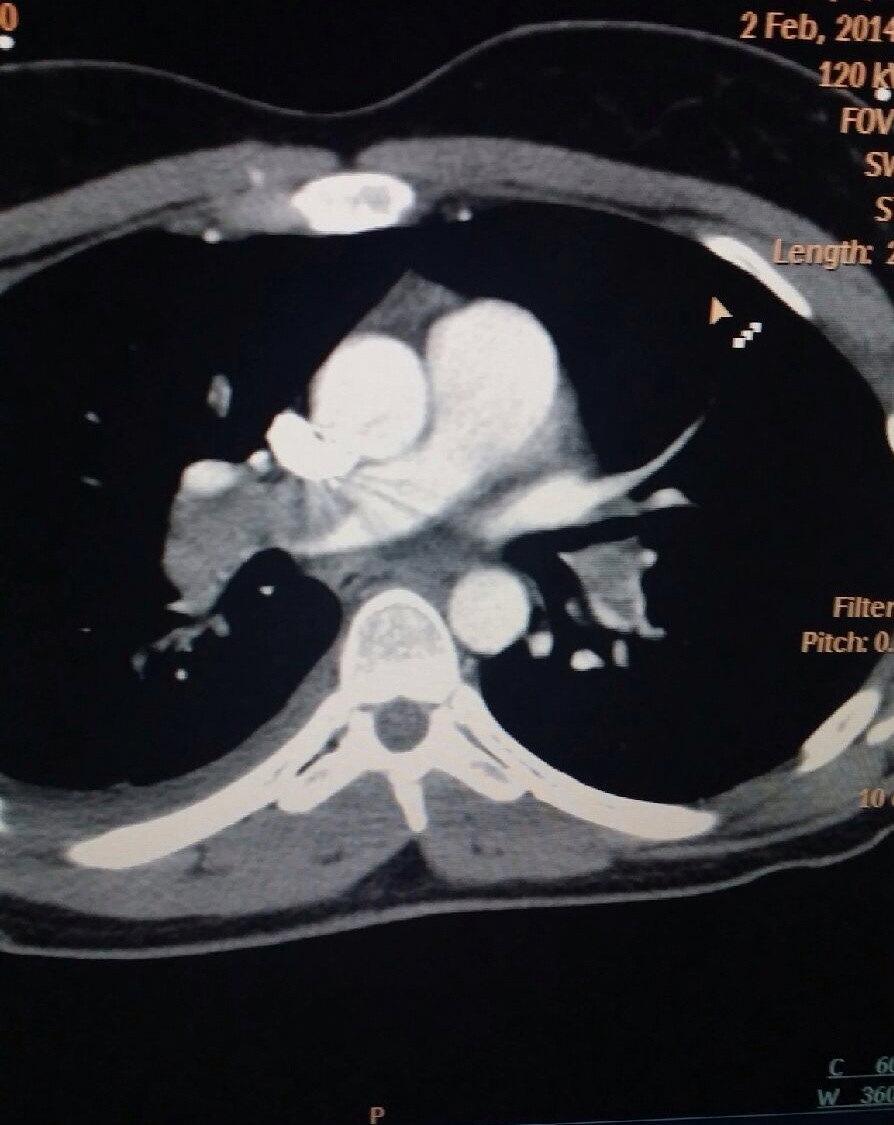

Its kind of crazy because I had felt a little sick for a few days before things drastically changed…I had been yawning a lot, not because I was tired, but more because I need more oxygen. It was bizarre and I didn’t think anything of it. I had also had a cough for about two weeks. I went to Barry’s on wednesday and noticed I had a harder time running than usual. I just chalked that up to my kind of cold symptoms. On Thursday morning when I went in to work I had the occupational health nurse take a look at my because I was having right sided chest/side pain. She said my lungs sounded clear, and that I might have pulled a muscle in my chest/side (which made sense after some of the moves we had done for chest day at Barry’s the day before) and she told me if my cough continued to come back and see her on MondayOn Thursday evening when I went to bed everything hit me like a ton of bricks. I couldn’t lay flat. It literally felt like I had a ton of bricks on my chest. I couldn’t breath. So I propped myself up to sleep semi upright. When I woke up Friday morning it was worse. I couldn’t even take 3 steps without getting short of breath. I was breathing so heavy. I didn’t really want to go to the doctor but my friend insisted that we go. All that was done was a chest x-ray and I was diagnosed with pneumonia and sent home with antibiotics. Saturday I did not feel any better and was so upset because if you know me, you know I LOVE Keith Urban! He was playing at the Bridgestone Arena and I had had tickets for months (floor seats too!). I really just wanted to find a wheel chair and go (haha) but I knew I would be miserable and not able to enjoy it anyway. That night I coughed up blood as well. That scared me. I did some research and saw that it could be a symptom of pneumonia. So then I didn’t really think much else of it. Sunday morning…after two days of antibiotics, I woke up feeling worse, not better. I knew that something was wrong and that the antibiotics should have been working by now. I called my parents and talked to them for a bit about what to do…we decided I would go to the Vanderbilt ER. As soon as I got in the door and they did an EKG, saw how low my oxygen level was (it was in the low 80s for all of your medical people), and my heart rate was high. The EKG confirmed their suspisions for a pulmonary embolism (or PE) but they wanted to do a Cat Scan to be sure and see the size of it. Now I am a Cat Scan tech and we scan a bunch of these tests a day…usually about 3% are positive…As soon as I was back in the room from my scan the doctor was waiting for me to confirm the CT showed a massive PE. I asked him to show me and sure enough I saw it with my own eyes. I have been doing Cat Scans for 4 years and I had never seen a PE that big!! They began their workup and prepped me for the OR. I didn’t even know that going in and physically removing the clots was even an option when a PE was this bad. They informed me I would have to have open heart surgery (yes my heart was stopped and it is scary to even think about) and I was put on a by-pass machine. Within the hour I was up in the OR and undergoing the surgery. I remember the doctor calling my parents to let them know what was going on. I vaguely remember the disbelief as the doctor had to repeat to them over and over what was about to happen and what they had to do to save my life. My parents hopped in their car and left Pennsylvania that night and headed down to Nashville.  The surgery took about 4 hours. I am so thankful my sister was there with me every step of the way. I remember waking up after surgery, still intubated (had a breathing tube down my throat)…and the Super Bowl was on. I was trying to spell/sign to her “score” with my fingers…I wanted to know who was winning! Haha! Shortly after I woke up they pulled the breathing tube out. I do not remember much of the next 12-24 hours because of the heavy drugs they had me on, but I was transferred out of the ICU and to a step down room for the rest of my recovery in the hospital.